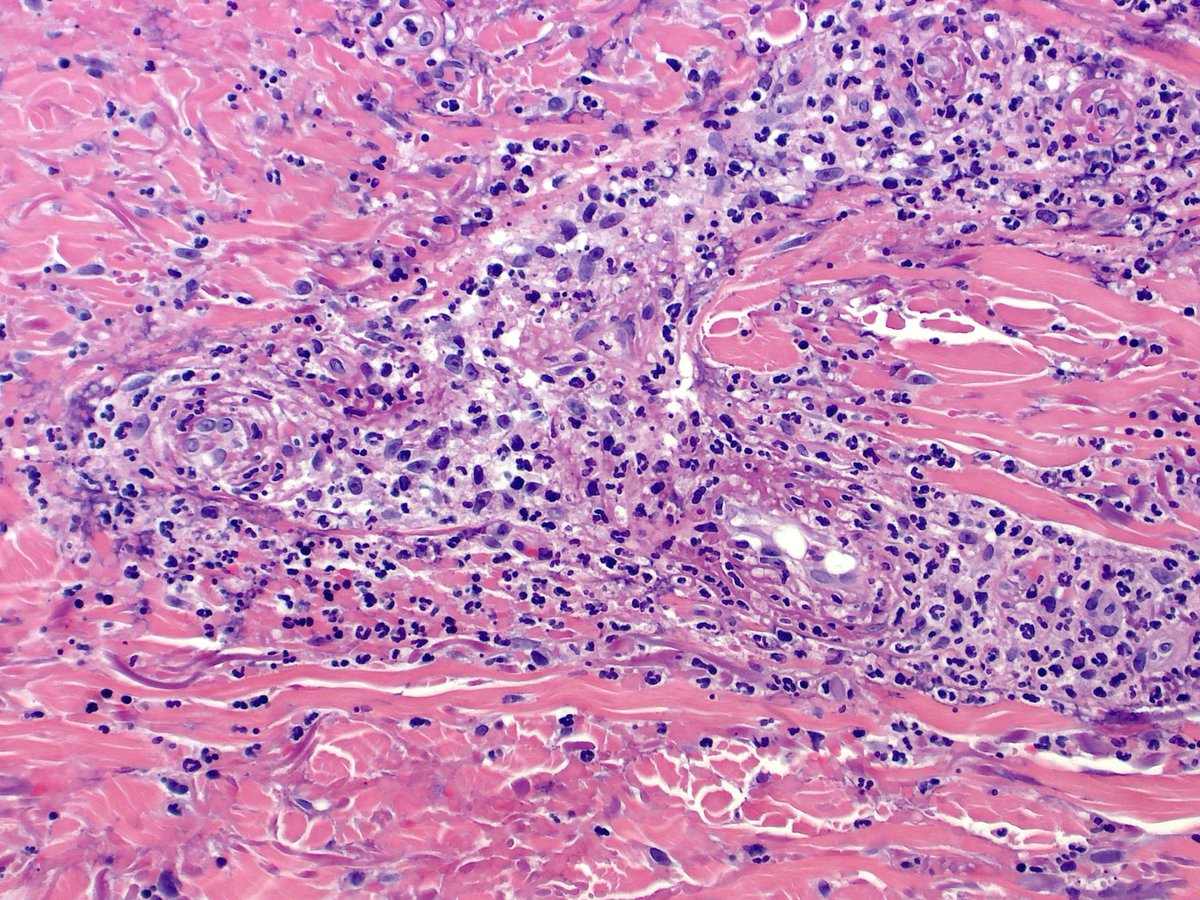

Cutaneous osteosarcoma? No, melanoma with osteoid formation. Most cases I have seen have been on the scalp, though some people see more mucosal or subungual cases. #dermpath #pathology #dermatology